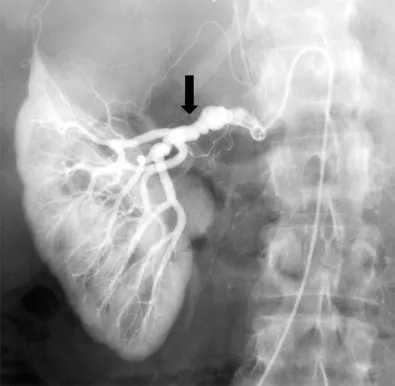

Amiloidose renal: aspectos sobre patogenia, diagnóstico e proteomica

Este vídeo apresenta, de forma didática e baseada em evidências, os principais achados da tese de doutorado sobre amiloidose renal, com foco em proteômica glomerular e ativação do complemento. São discutidos aspectos diagnósticos, implicações fisiopatológicas e correlações clínico-patológicas relevantes para a prática do nefrologista. O conteúdo sintetiza dados inéditos de matriz extracelular glomerular e diferencia perfis entre subtipos de amiloidose. Trata-se de um material aprofundado e acessível, ideal para atualização de especialistas na área.